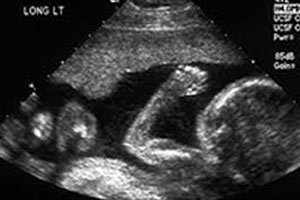

USG